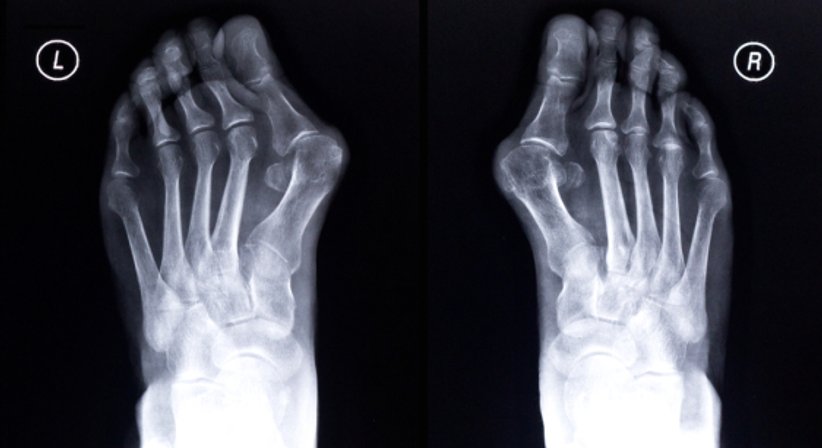

Hallux valgus

Der Hallux valgus ist eine fortschreitende Erkrankung des Vorfußes und die häufigste Fehlstellung der Zehen. Beim Hallux valgus ist die Großzehe nach außen in Richtung der kleineren Zehen abgeknickt, wodurch diese von ihrer Position verdrängt werden.